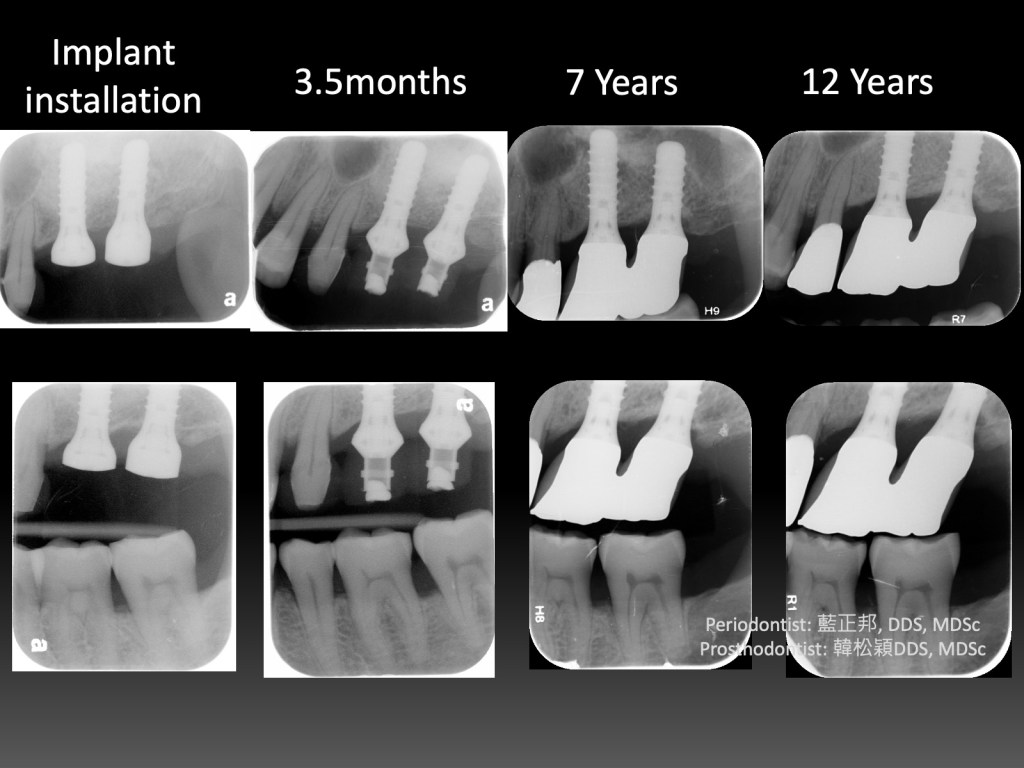

12 Years of Lateral-window Sinus Lift

2010年,台大第二年剛開始。這是我第一台鼻竇開窗手術,還記得很快地用骨刀切割,順利進入鼻竇。

但是翻到後面,遇到困難,只翻一半就遇到瓶頸,由台大老師接手翻完,之後回到我再放入材料並縫合。

這十二年來,口內狀態,加上X光檢查,一直都算穩定。但是回顧起來,病患其實血糖不低,加上抽菸,危險因子算多了。

如果其他的病患,危險因子一旦多,牙周穩定性會明顯變差,至少這個病患到現在為止還沒有。

到底是運氣好呢?還是有其他未知因素影響?又或許位於常態分佈—鐘型曲線兩端的極少數族群?

我也不知道。至少第一台十二年來慶祝一下~~